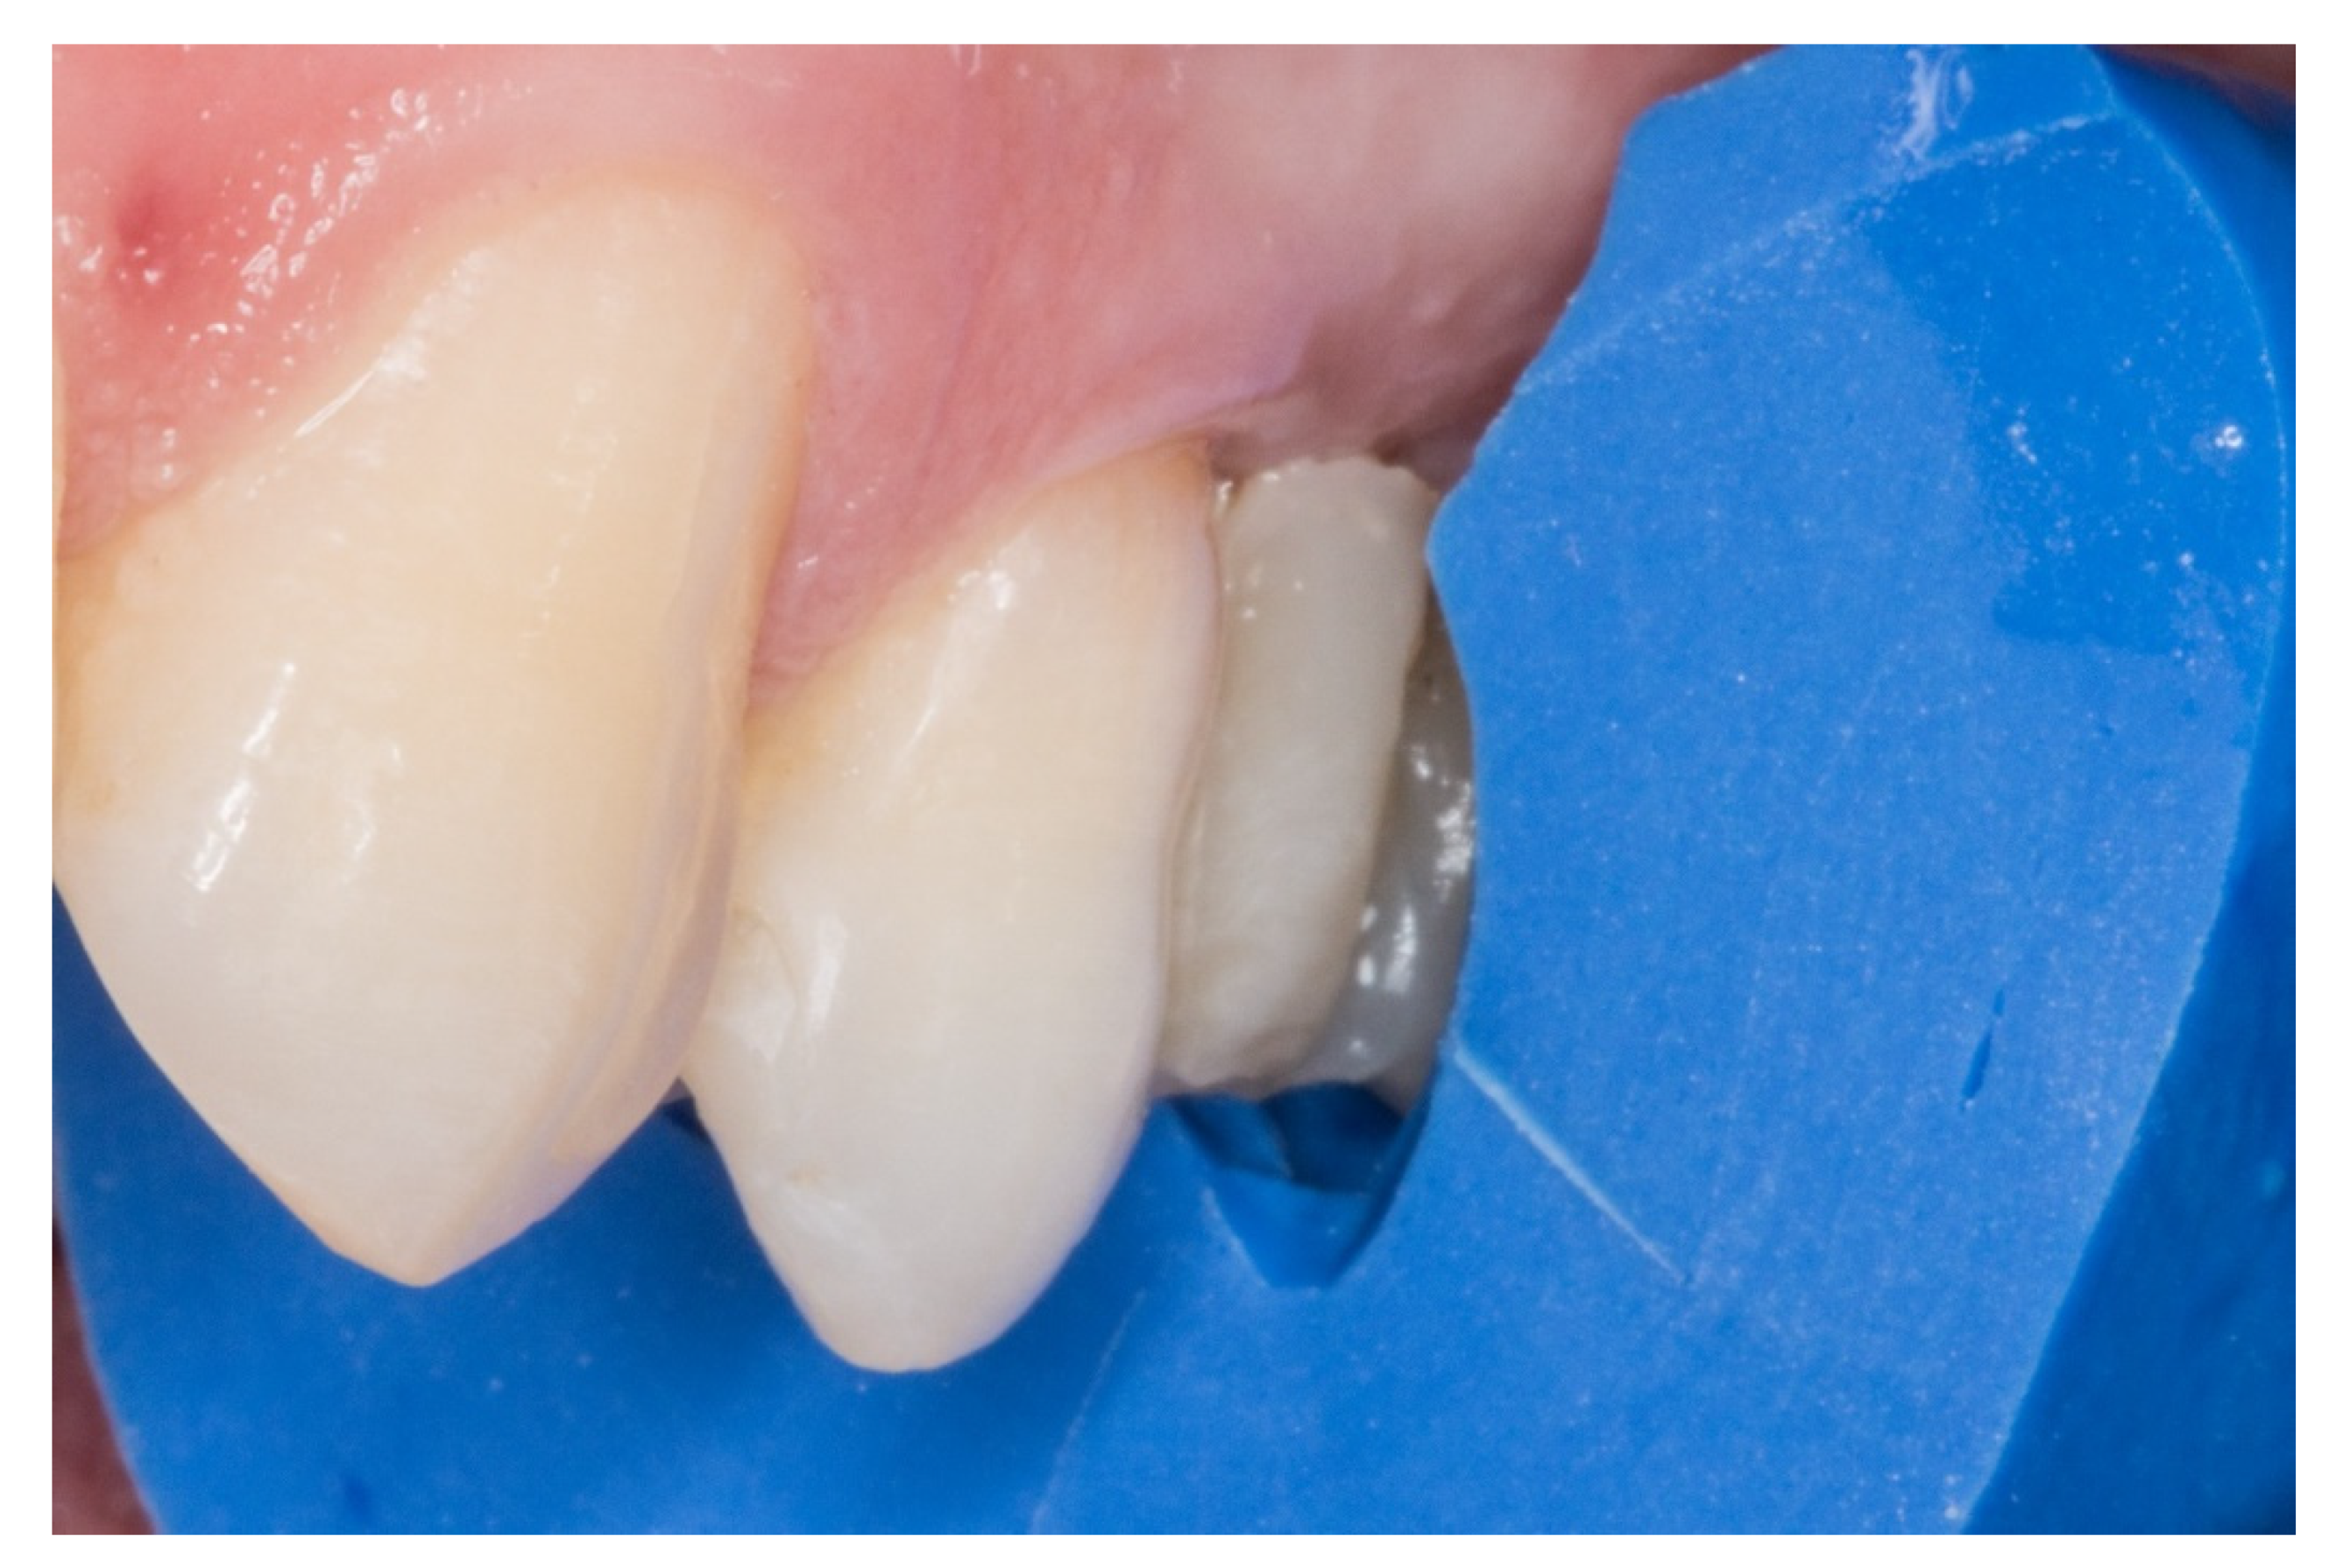

Figure 1.

A posterior maxilla edentulous space.

1. The new technique in “T” started once the silicone impressions of the patient were taken for both arches, and an interocclusal registration in the maximal intercuspation position was obtained, in order to prepare (on an articulator) the wax-up and the silicone keys for the tooth replacement [20]. Figure 1 represents the initial state of a case collected in the study.